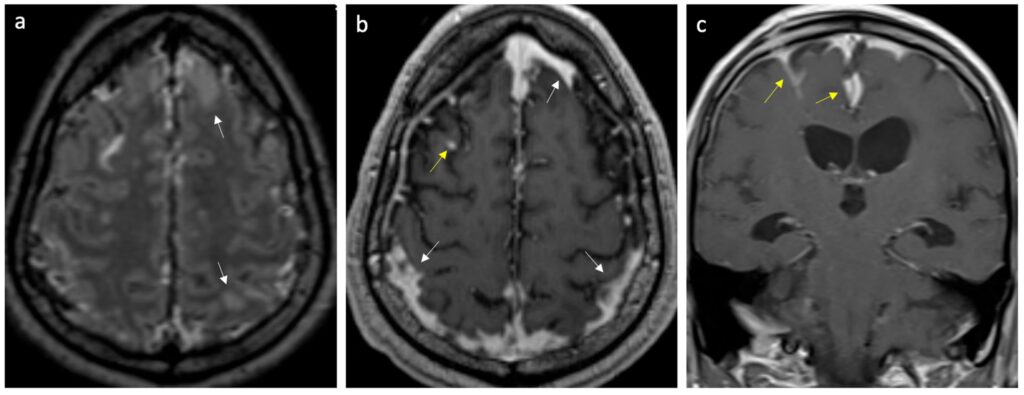

- Billeddiagnostik: En CT- eller MR-scanning af hjernen kan udføres for at udelukke andre årsager til symptomerne, såsom en hjerneblødning.